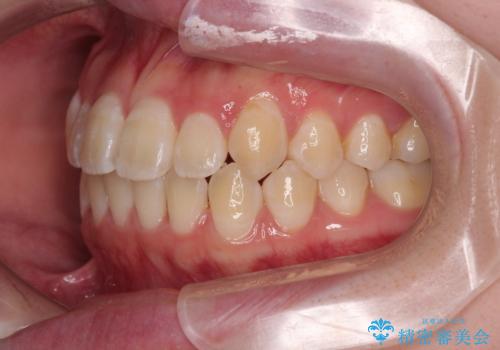

- 「前歯のデコボコ(叢生)をきれいに整えたい」とのことでご来院されました。

上下の正中(真ん中のライン)もずれることなく、バランスの取れた美しい歯並びに。笑顔に自信を持てる仕上がりとなりました。